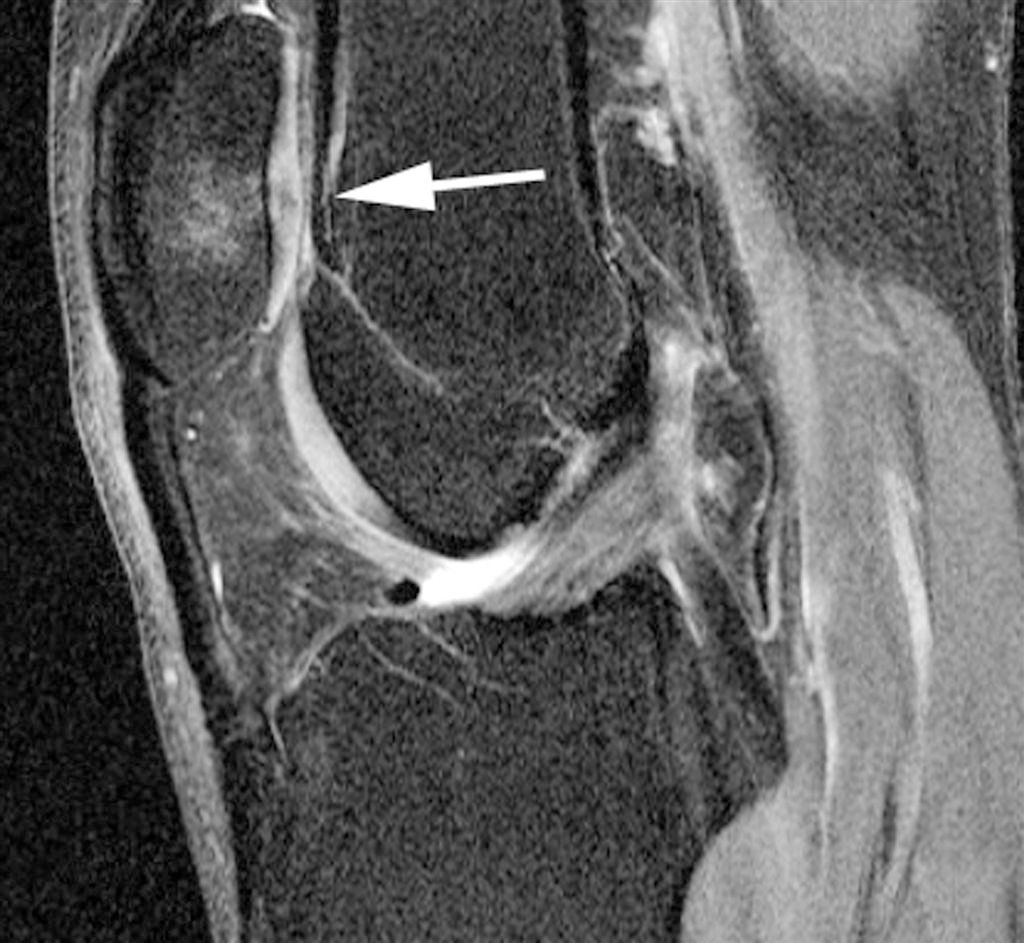

Using 3T MR imaging, California researchers have found that high levels of physical activity may be linked to knee abnormalities in middle-aged men and women. People between the ages of 45 and 55 who engage in several hours of walking, sports, or other types of exercise per week may be at greater risk of developing osteoarthritis than less active adults, according to a study presented Monday at the 2009 RSNA meeting.

Preoperative meniscal extrusion and the severity of cartilage loss and bone marrow edema can be trusted to predict the outcomes of arthroscopic partial meniscectomy in middle-aged and elderly patients.